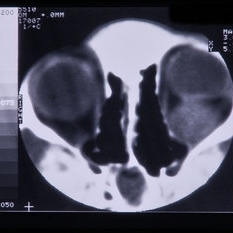

Rhabdomyosarcoma